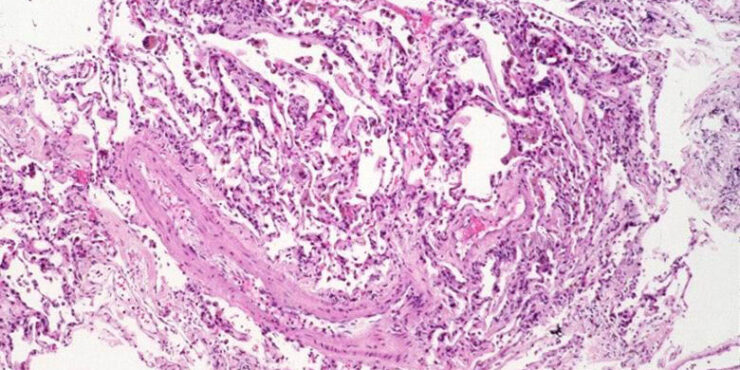

Read MoreNoninflammatory thrombi = الصمامة غير الالتهابية